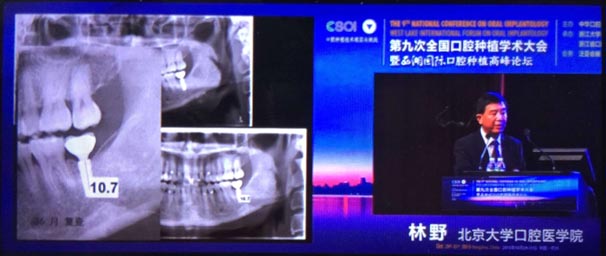

2015年10月29日第九次全國口腔種植學術(shù)大會暨“西湖國際”口腔種植高峰論壇在浙江省人民大會堂隆重開幕。這是中華口腔種植專業(yè)委員會主辦的兩年一度的全國性學術(shù)會議,代表了中國口腔種植學發(fā)展的水平和方向。

會議期間國內(nèi)知名口腔專家針對當前口腔種植領(lǐng)域熱點進行了精彩的學術(shù)演講。其中北京大學口腔醫(yī)學院林野教授的演講主題是“種植體設(shè)計及臨床意義”。

威高演講中林野教授對國產(chǎn)品牌WEGO牙種植體系統(tǒng)的設(shè)計和臨床表現(xiàn)表示肯定,向在座觀眾展示了WEGO牙種植體系統(tǒng)的臨床病例。病例對76枚WEGO牙種植體進行了平均21個月的追蹤觀察,結(jié)果表明WEGO牙種植體脫落、松動、種植體周圍病現(xiàn)象均為0,頸部骨吸收平均值為0.20mmSD值0.07。